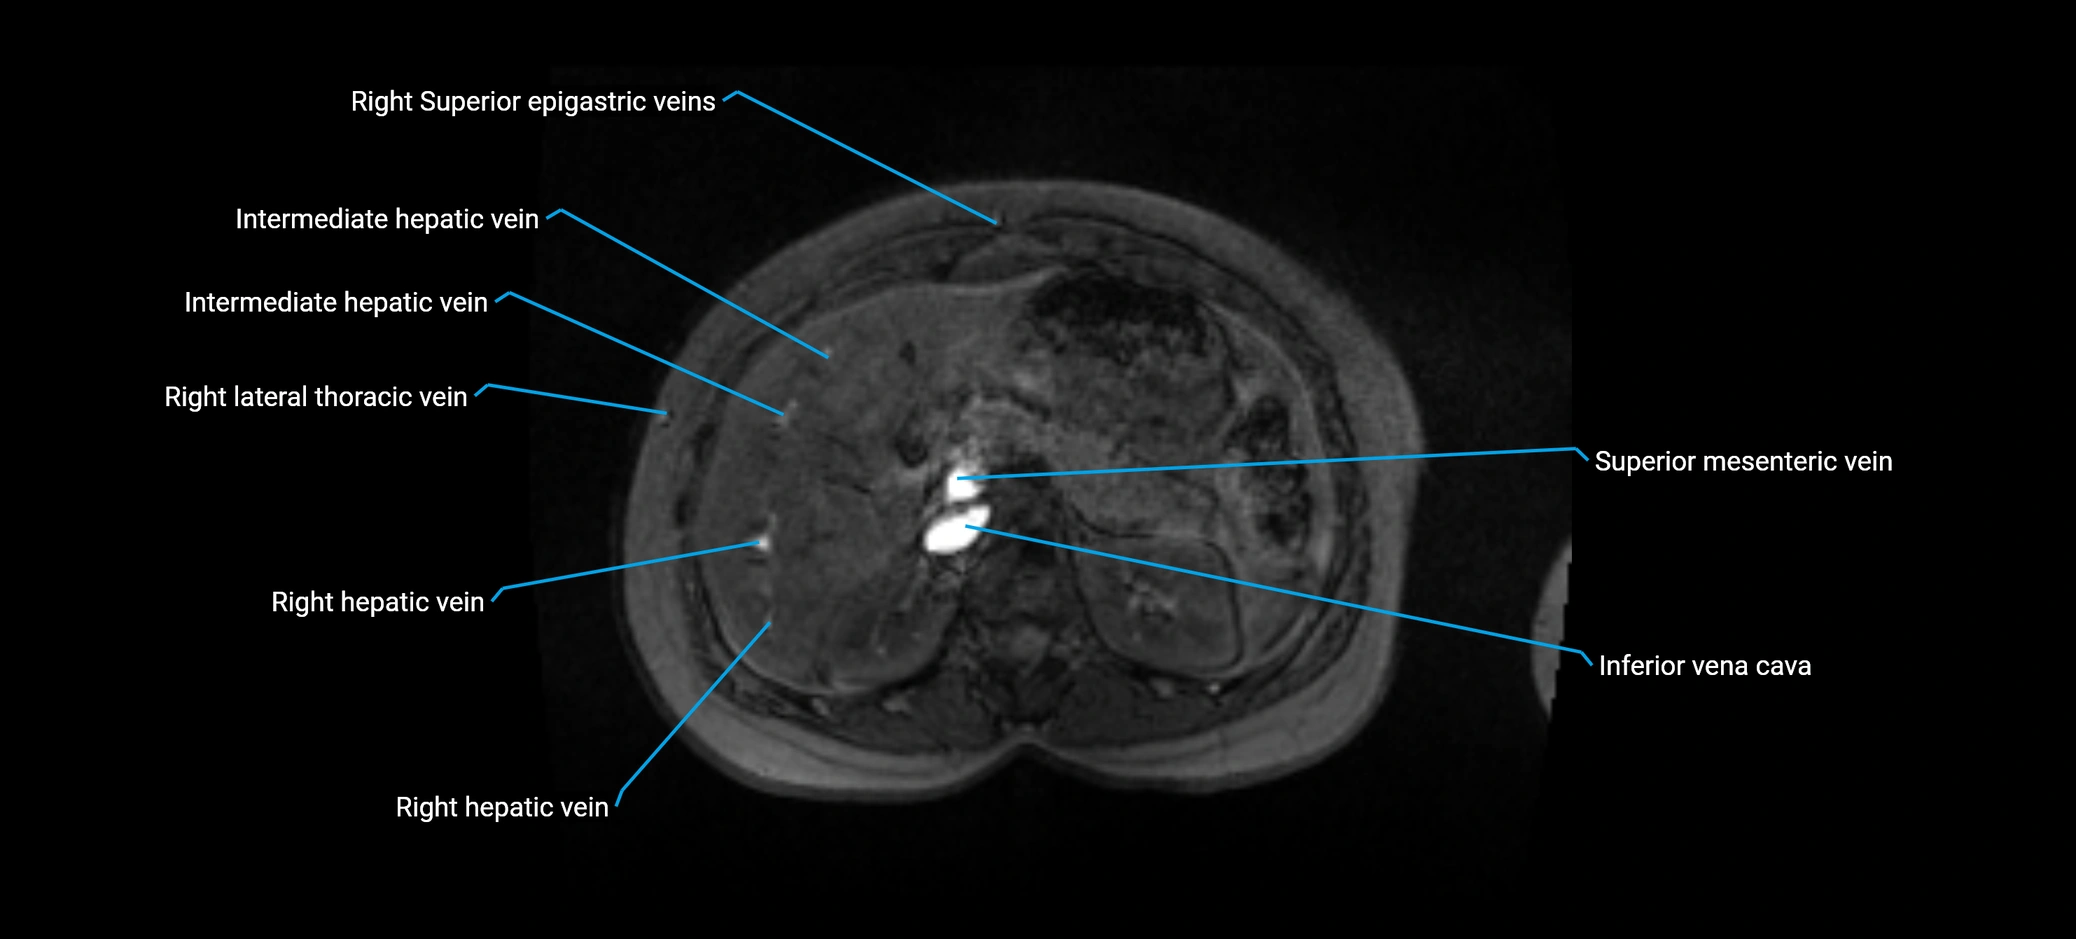

MRI image

image